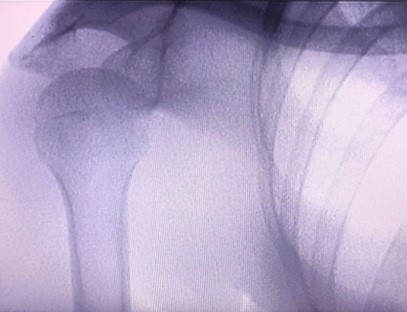

Ас-ц200 преносиви рендген апарат је преносиви инструмент са малом дозом зрачења и веома безбедан. Посебно је погодан за јединице и појединце са недовољним буџетом и ниским захтевима за слике. Нова генерација је опремљена великим екраном високе дефиниције од 10 инча, који има већи опсег перспективе и може у потпуности да посматра цео длан. Углавном је погодан за медицинску ортопедску перспективу. Може се повезати са филмским штампачем за штампање ортопедских филмова, а може се користити и у индустријској производњи и тестирању. Без мрачне коморе, директне перспективе, тренутног посматрања, високе резолуције и јасне слике.

Наш ортопедски рендгенски апарат је висококвалитетан производ који је дизајниран посебно за ортопедско снимање. Може се користити за дијагнозу и планирање лечења различитих ортопедских стања, укључујући фрактуре, дислокације, артритис и туморе костију. Опремљен је напредном рендгенском технологијом која омогућава висококвалитетне слике са смањеном изложеношћу зрачењу. Машина има систем за снимање високе резолуције и може да сними слике било које структуре костију са великом јасноћом.

1. Напредна технологија снимања: Наша ортопедска рендгенска машина користи напредну технологију снимања за снимање висококвалитетних слика костију и зглобова, пружајући тачне дијагнозе и побољшане резултате лечења.

Наш ортопедски рендгенски апарат се може користити у различитим медицинским специјалностима, укључујући ортопедију, неурологију и хитну медицину. Често се користи за флуороскопско посматрање костију људских удова, ветеринарске болнице и болнице за кућне љубимце, лечење рањеника на спортским местима, зградама, океанским бродовима, удаљеним подручјима и војним теренима. Неке од клиничких примена укључују: